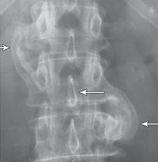

Рентгенограмма № 6

МРТ № 39

На рентгенограмме № 6 поясничного отдела позвоночника выраженный остеофитоз, спондилёз третьей степени, что также хорошо видно на МРТ № 39 поясничного отдела позвоночника